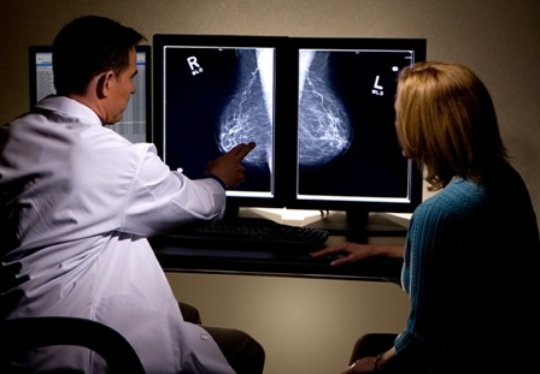

Diabetes y cáncer de mama

28 enero 2019

En las pacientes con diabetes tipo 2, las neoplasias de mama se diagnostican en estadios más avanzados; no se halló asociación con el tratamiento con insulina. Diabetes Care, 24 de enero de 2018